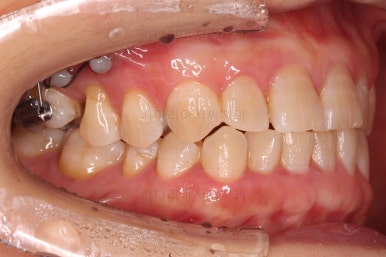

어금니를 뒤로 밀어주기 위해서 미니스크류와 브라켓, 철사를 이용해줘요.

중간중간 장치 디자인이나 미니스크류의 위치를 바꿔주기도 하고요.

점점 자리가 확보되어가는게 보이시죠?